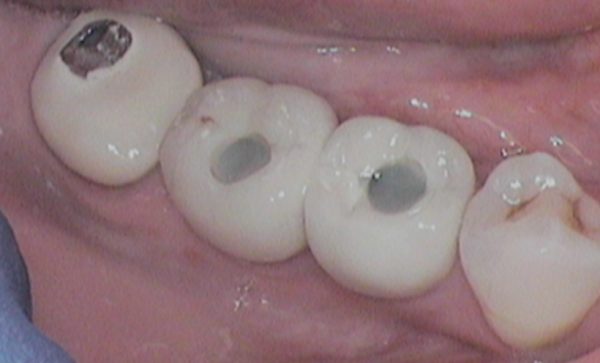

Case 10